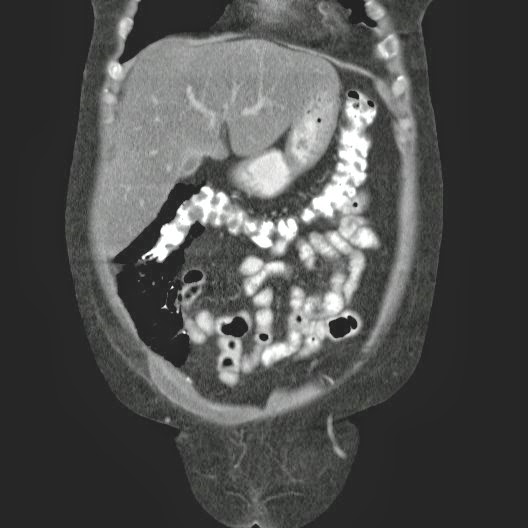

Paciente con antecedente de ALIF (Fusión lumbar intersomática anterior) 360 grados L5-S1 hace siete meses, quién presenta herida de abordaje anterior con dehiscencia de sutura, con cierre por segunda intención, quien consulta por cuadro clínico de dos días de secreción purulenta en herida quirúrgica, niega fiebre, niega otras sintomatología, refiere episodios previos similares.

Paciente en POP de ALIF L5-S1 quien presento dehiscencia de la herida abdominal con ISO superficial ya tratada, sin embargo persiste con dehiscencia y desde ayer con supuración asociado a fiebre subjetiva. Se realiza eco abdominal con colección en pared sugestiva de absceso, elevación de RFA por lo cual se considera se debe hospitalizar para manejo antibiótico, drenaje de la colección, manejo médico y vigilancia neurológica.

- ¿Hallazgos Escanografia?

2. Hay una colección de la pared abdominal en el flanco derecho, que realza en la periferia con el contraste, e intraabdominal tiene aire pero no me parece colección intraabdominal porque la grasa no está alterada.